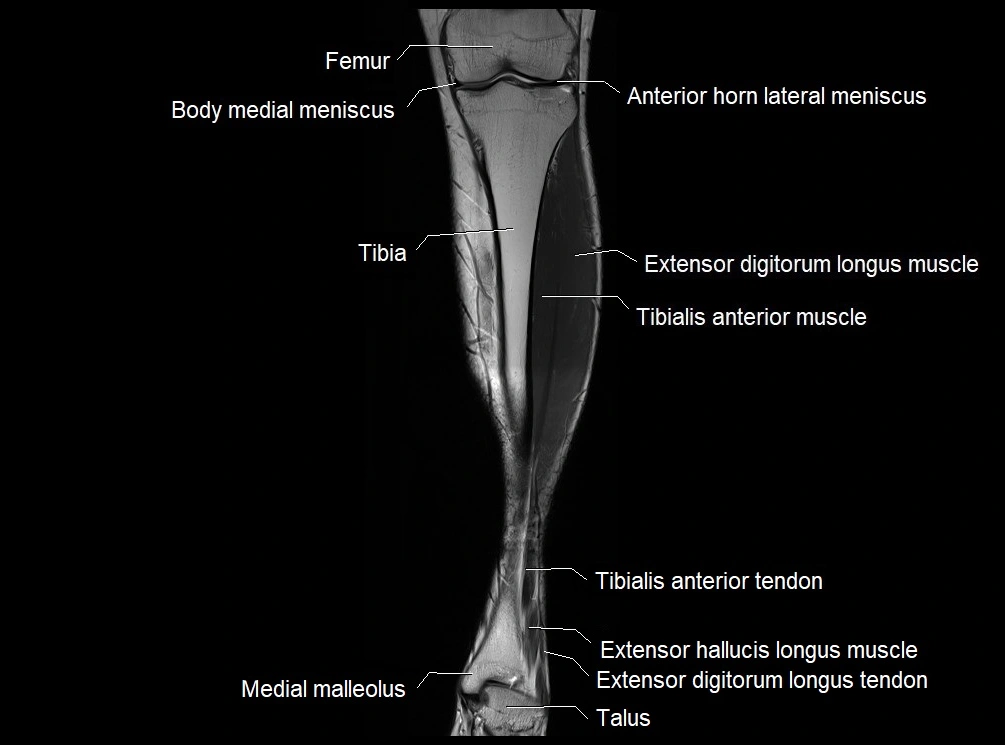

MRI image